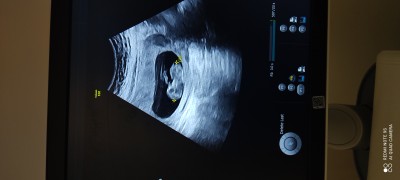

11+5 cinsiyet tahmini yaparmisiniz

image